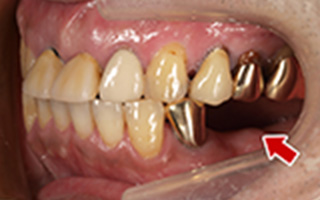

Before

After

| 55歳 男性 | |

|---|---|

| 主訴 | 前歯でしか咬めなく、食事を摂るのに非常に困難で辛い |

| 処置内容 | 上顎6本、下顎3本 |

| 治療費用 | 上顎: 約230万(税込) 下顎: 約120万(税込) |

| 治療期間 | 上顎: 1年(仮歯まで8ヶ月) 下顎: 8ヶ月(仮歯まで5ヶ月) |

| リスク | 上部構造物、仮歯の破折、術後の腫れ(3日)、人工歯根脱落リスクがあります |